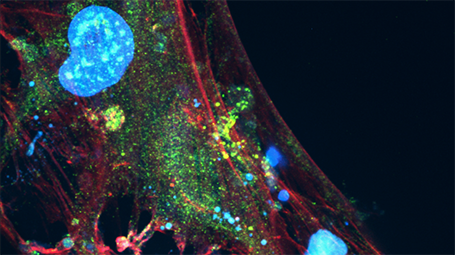

La ingeniería regenerativa es un campo nuevo y emocionante que se define como la convergencia de los avances en la ciencia e ingeniería de materiales, células madre y biología del desarrollo, ciencias físicas y la aplicación clínica para desarrollar herramientas escalables y confiables que permitan la regeneración ó reconstrucción de tejidos complejos y órganos. Puede considerarse un campo que busca facilitar la implementación de la medicina regenerativa para todos.

Con este objetivo, profesores de la Escuela de Ingeniería McCormick y de la Escuela de Medicina Feinberg convergen para participar en investigaciones y educación a través del Instituto Querrey Simpson de Ingeniería Regenerativa de la Universidad Northwestern (QSI RENU), que liderará la iniciativa para desarrollar y traducir tecnologías transformadoras que capaciten a nuestro cuerpo para sanar.